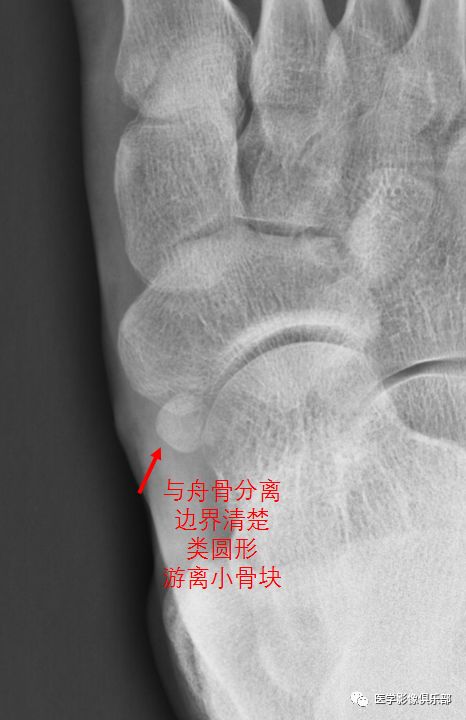

2型副舟骨和舟骨结节间以纤维软骨相连,受到外伤后关节损伤,出现炎症。